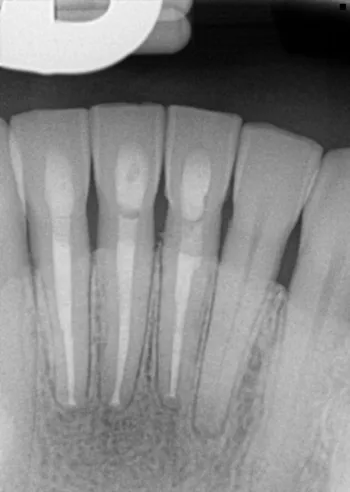

Before

After

Patient is a 62 year old male. Patient was seen for retreatment of teeth 7 and 8 procedure completed on 4-29-24. He was seen 6 months post treatment and CBCT with comparison was taken. Apicoetomy surgery was recommended on teeth 7 and 8 and was completed 11-11-24. Final x-ray is from 1-20-26.